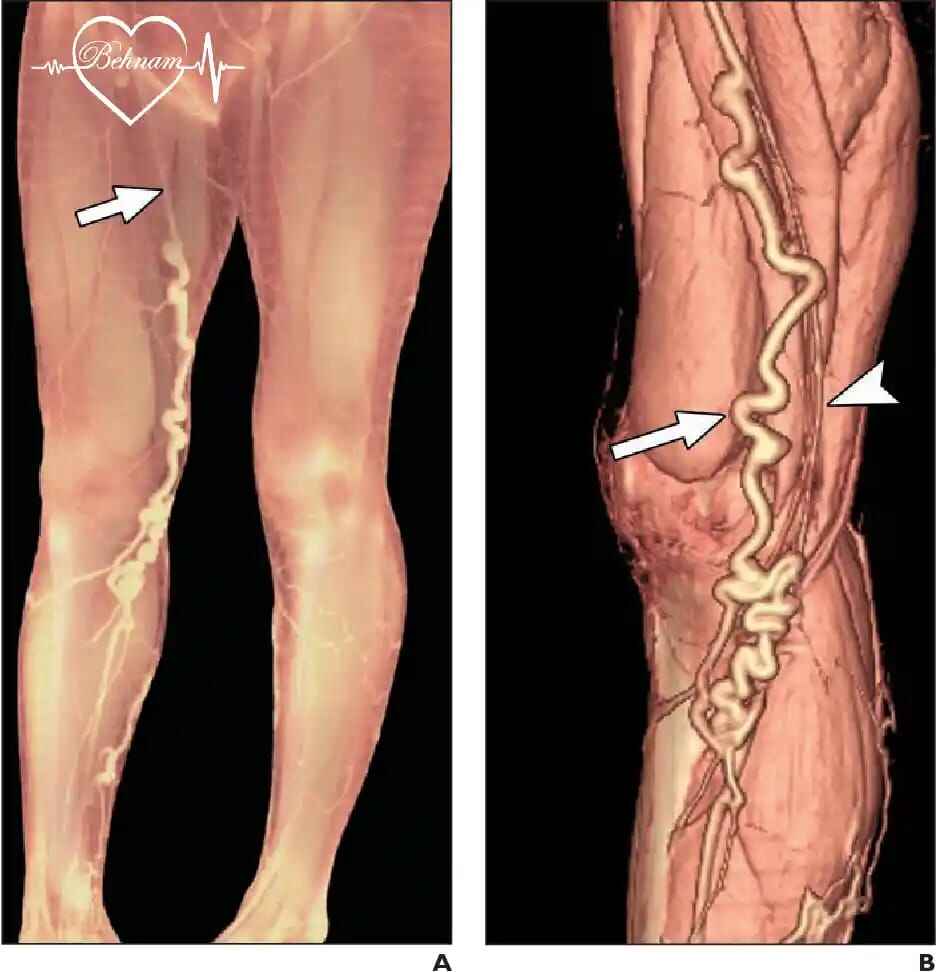

دکتر بهنام واقفی یکی از جراحان بسیار با تجربه در زمینه واریس و قلب می باشند که در کلینیک فوق تخصصی خود با استفاده از به روزترین و مجهزترین دستگاه ها و روش های نوین به درمان بیماران می پردازند.